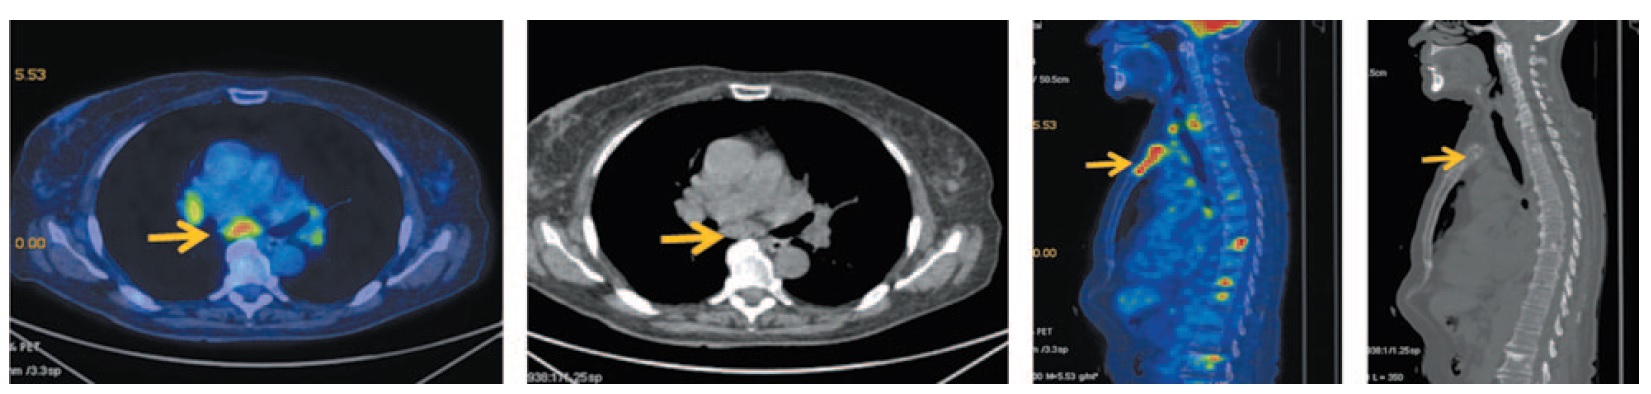

Кроме того, по данным ПЭТ/КТ выявлены множественные медиастинальные лимфатические узлы размером до 15 мм с повышенной фиксацией 18-ФДГ, SUVmax 5,0. Во всех костных структурах отмечается картина смешанной, преимущественно бластической, перестройки, SUVmax 7,65 (рис. 3).

Рис. 3. Больная Б., 72 года, до лечения. На аксиальных и сагиттальных ПЭТ/КТ проекциях определяются множественные медиастинальные лимфоузлы (паратрахеальные верхней и нижней группы, бронхопульмональные с двух сторон, бифуркационные), размером до 15 мм с повышенной фиксацией ФДГ с SUVmax 5,0. Во всех костных структурах зоны сканирования на фоне смешанной перестройки костной ткани (преимущественно бластической, в грудине – литический характер) отмечается очаговый гиперметаболизм ФДГ SUVmax 7,65. / Fig. 3. A 72-year-old woman before the treatment. Axial and sagittal PET/CT images show multiple mediastinal lymph nodes (upper and lower paratracheal, bronchopulmonary on both sides, bifurcation groups of lymph nodes) measuring 15 mm with increased uptake of FDG SUVmax 5.0. In all bone structures of the scanning zone against the background of mixed bone remodeling (mostly blastic lesion, in the sternum – lytic metastatic lesion) with focal increased RFP uptake SUVmax 7.65.